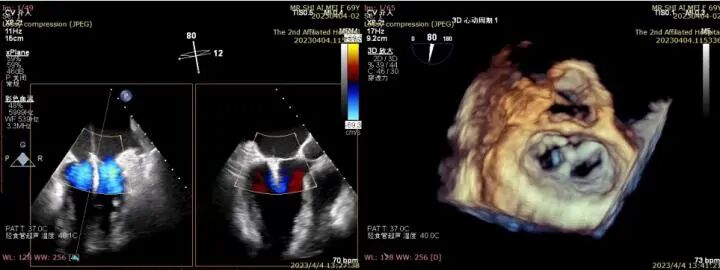

△完全在超声引导下完成二尖瓣夹的定位、瓣叶抓取和二尖瓣夹的释放

△三维超声确认夹合位置理想